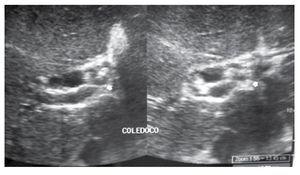

Mujer de 36 años, sin antecedentes relevantes salvo haber presentado un cuadro de probable hepatitis viral A cuatro años antes de su ingreso. Su padecimiento se inició tres semanas antes con fiebre precedida de escalofríos y poco después, ictericia progresiva no dolorosa y coluria intermitente sin prurito. Dos días antes del ingreso desarrolló edema de las extremidades inferiores y astenia importante. Su médico de primer contacto ordenó un ultrasonido abdominal que demostró hepatomegalia, dilatación de vías biliares intra y extrahepáticas, pared vesicular de 4 mm, imagen litiásica con sombra acústica, varias imágenes ovoideas en la vía biliar extra hepática sin sombra acústica que hicieron sospechar en la presencia de fasciola y esplenomegalia de 15 cm (Figura 1). A su ingreso se encontró a la paciente con 38°C de temperatura corporal, peso 60.2 kg, estatura 153 cm. Ictérica, con hepatomegalia de 6 cm por abajo del reborde costal, sin bazo palpable, con edema discreto de los tobillos y de los pies. Los exámenes mostraron Hb 11g/dL, bilirrubina total 7.93 mg/dL, bilirrubina directa 4.7 mg/dL, AST 69 U/L, ALT 42 U/L y fosfatasa alcalina 387 U/L. Se solicitaron anticuerpos antinucleares, anti-musculo liso, anti-mitocondriales y anti-virus Epstein Barr siendo todos negativos.

¿ Figura 1. Dilatación de vías biliares, la flecha señala las probables fasciolas.

En nuestro caso, el ultrasonido fue insuficiente para establecer un diagnóstico preoperatorio preciso ya que demostró la dilatación de las vías biliares intra-hepáticas y reportó erróneamente la dilatación de las vías extra-hepáticas estableciendo la sospecha de infestación por fasciolas, mismas que correspondieron a ganglios linfáticos hipertróficos. Mediante el estudio de ultrasonido no se sospechó de la anomalía congénita del conducto hepático común que desembocaba en el cuerpo de la vesícula. Esto es consistente con otros los informados en la literatura, ya que todos han sido hallazgos operatorios,1,2 excepto el más reciente que fue un hallazgo post mortem.3 La tomografía y la colangio-resonancia magnética nuclear son dos estudios potencialmente útiles para identificar anomalías de las vías biliares en pre-operatorio,4-7 pero no fueron practicadas en este caso es particular.